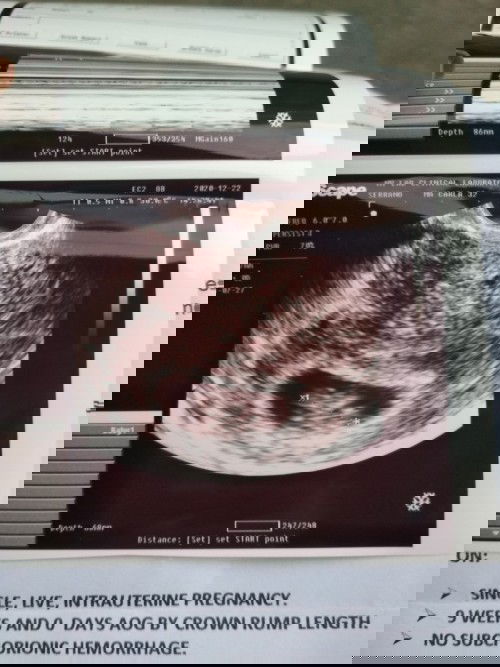

2nd TVS. Finally! Nakita din heartbeat ni baby. 1st TVS ko 5 wks 4 days gestational sac palang so I was a bit worried. I kept on praying na sana ok ang baby ko. A week after maconfirmed na pregnant ako thru TVS, my dad passed away. Sobrang stressed ako nun nag-alala lalo ako for my baby's health. Kaya nung nakita ko yung heartbeat niya for the first time today, naging emotional ako pero mas naging masaya. Sadly, di na makikita ng dad ko ang first apo niya. Matagal na niya kong kinukulit na gusto na niya magkaapo. I'm in my 30s na din kasi and this is my first baby. Sayang.. 😢#1stimemom #firstbaby